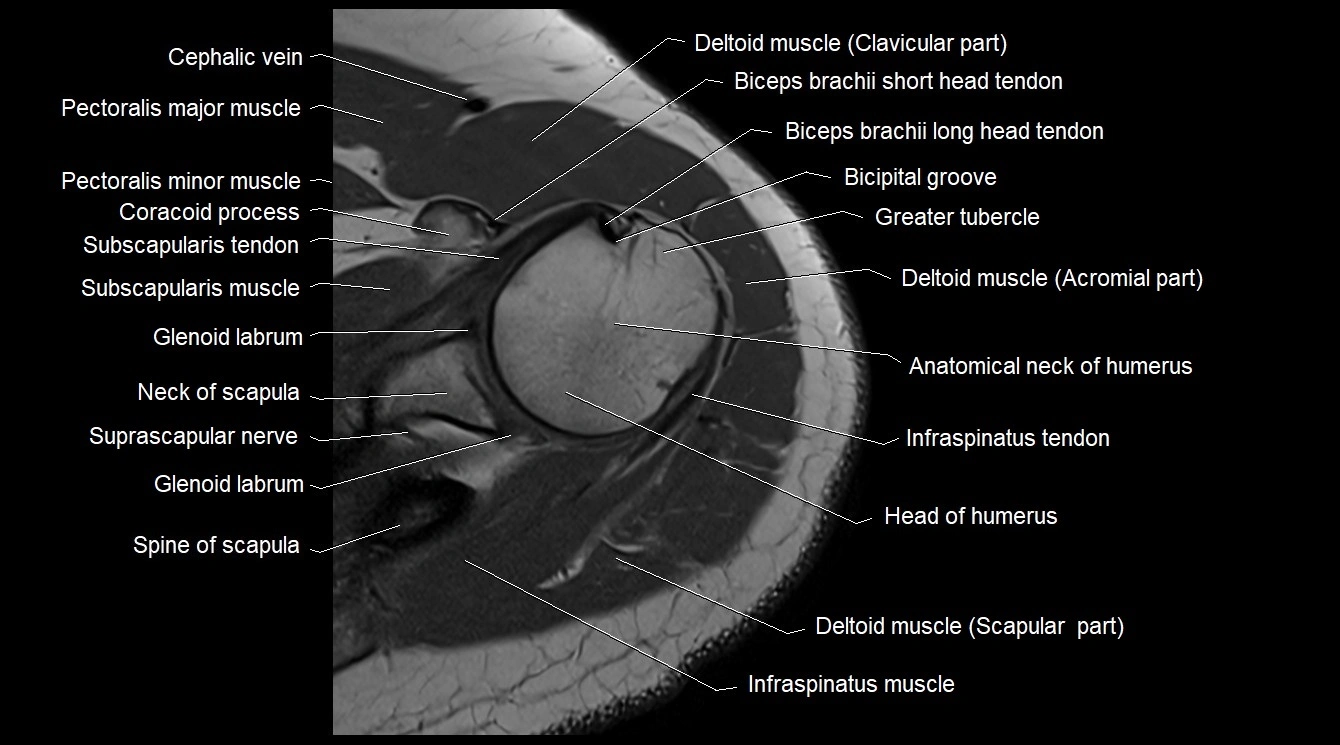

- Anatomical neck of humerus

- Bicipital groove

- Cephalic vein

- Clavicular part of deltoid muscle

- Coracoid process of scapula

- Glenoid labrum

- Greater tubercle of humerus

- Head of humerus

- Infraspinatus tendon

- Long head of biceps brachii muscle

- Long head of biceps tendon

- Median nerve

- Neck of scapula

- Pectoralis major muscle

- Pectoralis minor muscle

- Spine of scapula

- Subscapularis muscle

- Subscapularis tendon